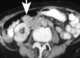

Brunner gland hyperplasia

Brunner's glands (or duodenal glands) are compound tubular submucosal glands found in that portion of the duodenum which is above the hepatopancreatic sphincter (i.e sphincter of Oddi). The main function of these glands is to produce a mucus-rich alkaline secretion i.e. [Source: Wikipedia ]